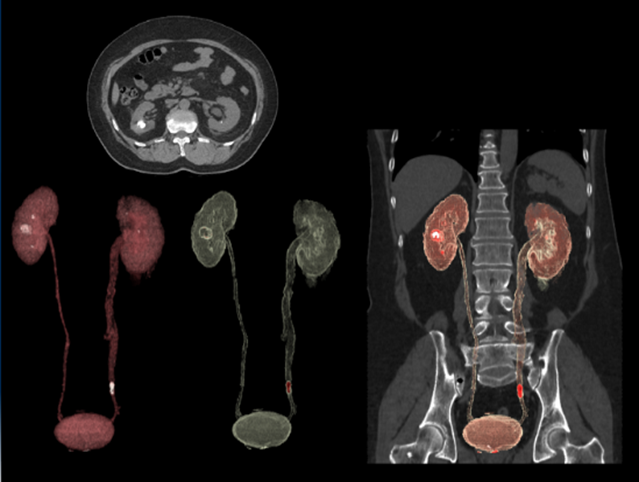

体幹部の検査においても、単純CTのアキシャル面から3D構築ができるため、幅広い視野で観察可能になり、転移の様な多臓器の観察にも有用であると考えています。

cv_uchida_06_big.png

非造影3D     造影後の3D

また、別の症例では、さすがにワンクリックではありませんが、非造影による単純スキャンデータから3D解析ツールを駆使して、このような尿路系の3D画像を構築することもできました。これも患者様に症例の解説を行う際にたいへん有用でした。

cv_uchida_07_big.png